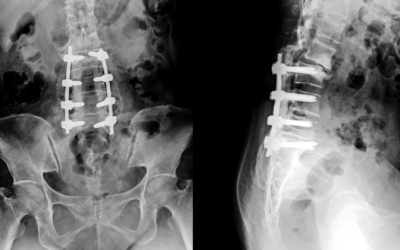

Advanced Bone Plate Technology: Dynamic Compression and Locking Solutions

The field of orthopedic traumatology has witnessed a tectonic shift in how fractures are managed. From the rudimentary splints of the past to the sophisticated internal fixation devices of today, the primary goal remains the same: restoring anatomical alignment and...